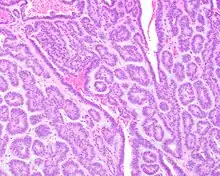

Canalicular adenoma growths are usually small at the time they are noticed, with an average size of about 1.6 cm.[1] Their histologic appearance is very distinct, with a channel-like pattern between cords and ribbons; the pattern has been described as resembling a "string of pearls."

The growths often contain are often small bight squamous balls, or morules. They also typically contain a well-developed supporting tissue - a fibrous stroma - which is rich in hyaluronic acid and chondroitin sulphate.[1] In a few cases, the growths may contain small calcium deposits or microliths. Although it is seldom necessary, a pathologist can confirm the existence of canalicular adenoma through immunohistochemistry studies, with the cells reacting with pancytokeratin, S100 protein and SOX10, with a delicate GFAP reaction around the periphery.[5][1][6][7] Although it is a benign tumor, a positive diagnosis of canalicular adenoma may be necessary to exclude the existence of other medical conditions such as a basal cell adenoma, pleomorphic adenoma, adenoid cystic carcinoma, and polymorphous adenocarcinoma.